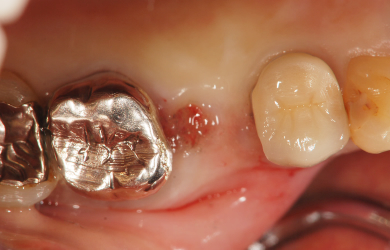

治療後

• 治療後

インプラント埋め込み施術は外科治療のため、腫れる可能性があります。細菌感染すると施術のやり直しになりますが、当院では洗浄・滅菌を徹底して感染リスクを抑えます。また、インプラント周囲炎にならないために、通常の歯と同じように丁寧なブラッシングや定期メンテナンスが重要となります。